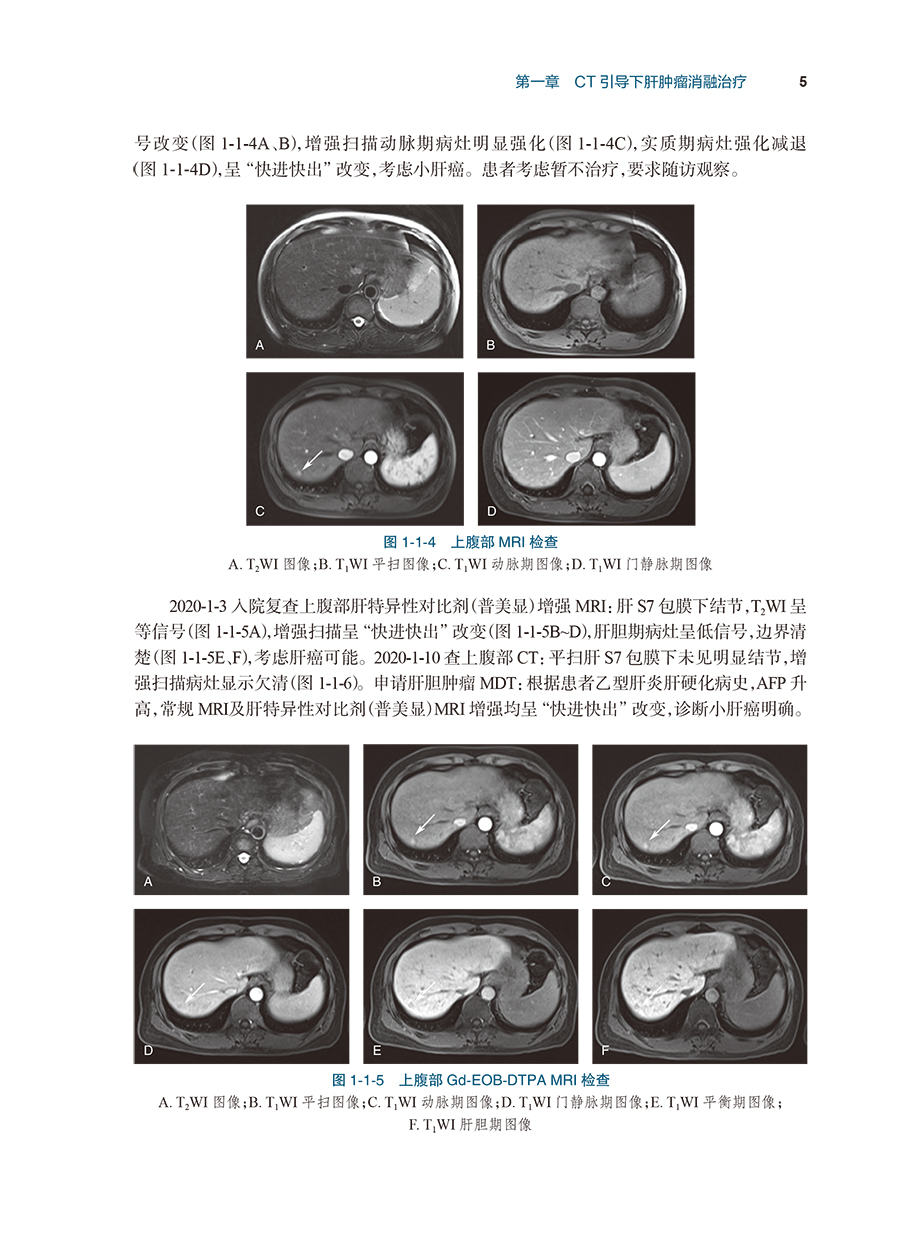

病例2TAE碘油标记后序贯微波消融治疗小肝癌/4

病例3肝包膜下小肝癌的微波消融治疗/8